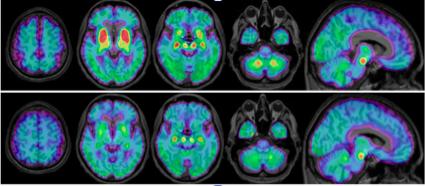

image: PI-2620 binding expressed as distribution volume ratios from multilinear reference tissue modeling 2. Axial and sagittal slices from averaged groups of PSP-RS (upper row) and healthy controls (lower row) are depicted upon an MRI template.

In the study, researchers utilized a novel second-generation radioligand, 18F-PI-2620, to evaluate patients with suspected tau pathology in clinically diagnosed PSP. Seventeen patients with probable or possible PSP underwent 18F-PI-2620 positron emission tomography (PET) imaging at four different health care centers, along with 10 healthy control patients and seven disease control patients who had multi-system atrophy, Parkinson's disease or Alzheimer's disease. Standardized uptake value (SUV) ratios of 18F-PI-2620 in predetermined brain areas were obtained and compared between the PSP, healthy control and disease control patients. In addition, disease severity, measured by the PSP rating scale, was correlated with PET findings.

A significantly elevated mean 18F-PI-2620 SUV ratio was found in the globus pallidus and the substantia nigra areas of the brain in the PSP patients as compared to the healthy control group. In contrast, the disease control group showed similar or only slightly elevated SUV ratios when compared to the healthy control group. Furthermore, results showed that even patients with low disease severity already had significantly elevated 18F-PI-2620 uptake in the globus pallidus when compared to the healthy control group.

"My colleagues and I were able to detect an elevated signal in the majority of evaluated PSP patients and could clearly discriminate the PSP group from healthy controls and disease controls," noted Brendel. "Importantly, PSP patients at early disease stages also revealed an elevated PI-2620 signal, which points at the suitability of this ligand as an early PSP biomarker. Detection of tau in PSP patients by PI-2620 could play a role in future anti-tau trials for this disease, and molecular imaging could serve to select the right patients for targeted therapies."